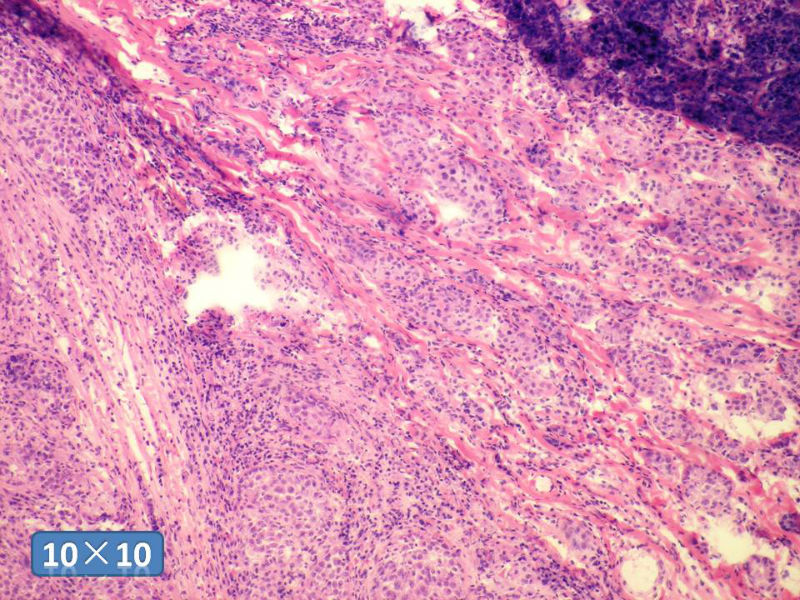

女性,50岁,乳腺肿物,冰冻切片(图1-25)

HE